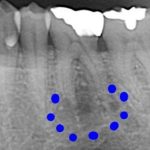

歯が無い所にインプラントを入れたい

治療前 治療後 年齢・性別 60代 女性 相談内容 歯が無い所にインプラントを入 ...